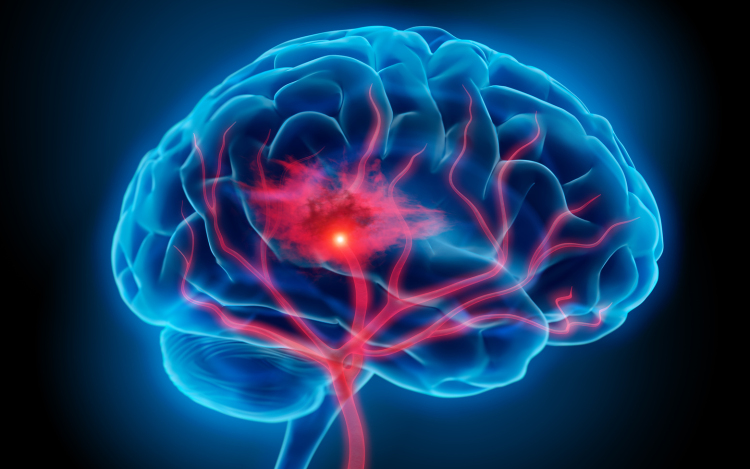

Óránként egy halálesetért a stroke felelős

Magyarországon évente 45 ezren kerülnek kórházba stroke miatt, óránként egy halálesetért felelős a betegség - mondta Bereczki Dániel, a Magyar Stroke Társaság elnöke az M1 aktuális csatornán szombat este.

Hozzátette, ma már tízezer alatt van azoknak a száma, akik belehalnak a stroke-ba, ami jelentős csökkenés 1980-hoz képest, amikor évente mintegy 24 ezren haltak meg ebben a betegségben.

Mint mondta, ennek oka, hogy az emberek egyre komolyabban veszik a kockázati tényezőket, elsősorban a magas vérnyomást, cukorbetegséget, a szívritmuszavart, és a magatartásbeli tényezők között a dohányzást.

Nem csak az idősebbek vannak kitéve a stroke veszélyének, Magyarországon az esetek több mint 10 százaléka 50 éves kor alatt, több mint 27 százaléka munkaképes korban jelentkezik - mutatott rá.

Kitért arra, hogy a stroke három fő tünete, amikor azonnal mentőt kell hívni, mert 3 óra van az eredményes beavatkozásra, az egyik oldali végtag meggyengülése, a száj félrehúzódása és a beszéd elakadása.

A szakértő elmondta, a betegek csak 5 százaléka kapta meg a vérrögoldó kezelést tavaly, mert későn mentek kórházba. Az európai átlag 10 százalék, tehát vannak még feladatok - jegyezte meg.